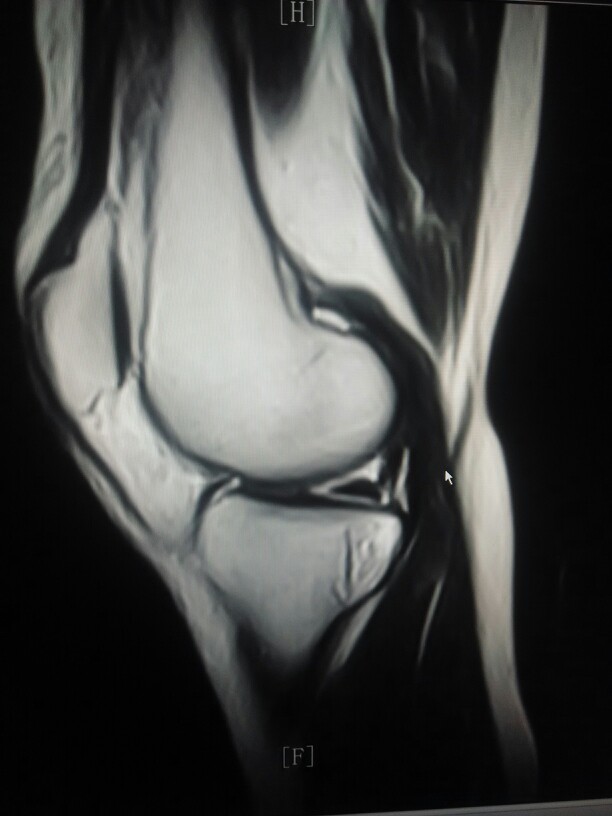

女性患者,50岁,右侧膝关节,出现肿痛,关节受限2年,加重2月。既往没有其他病史没有做过,膝关节的x光片,ct检查,近日来我院就诊,查膝关节的核磁共振扫描显示。右侧胫骨内侧平台下方可见片状稍长t2信号。外侧半月板后角可见小片状稍长t2信号影。关节腔内可见积液信号。大家讨论一下该病人胫骨平台是骨髓水肿还是其它病变。

接上个病例,女性,50岁,右侧膝关节肿胀活动受限2年